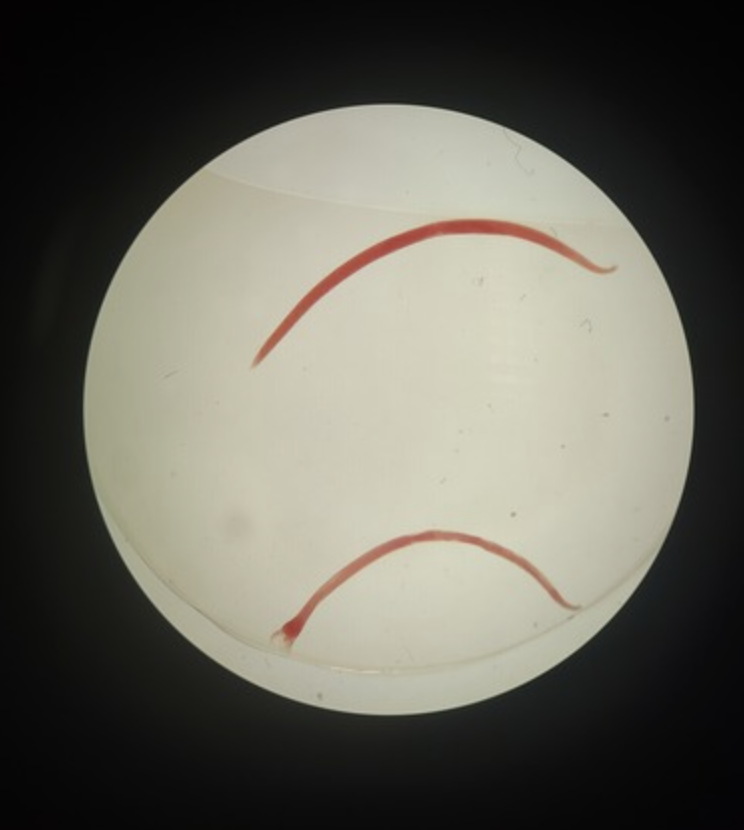

Trichuris trichuiura ๐

fecal-oral ๐ฉ

egg

human